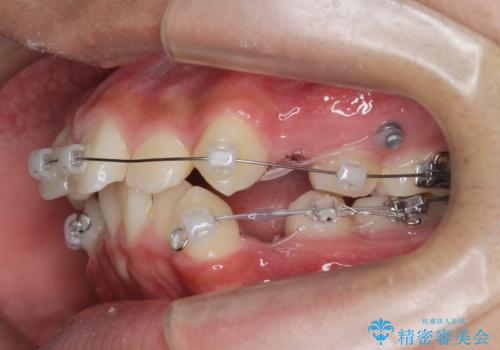

- 前歯のがたつきが原因で歯ブラシしづらい、見た目を改善したい!と矯正治療を希望され来院されました。

スペースの不足が見られるため、小臼歯の4本抜歯を行いマルチブラケットを用いた矯正治療を計画します。

噛み締めが強く、治療に時間がかかりましたが矯正治療の仕上がりに満足いただくことができました。